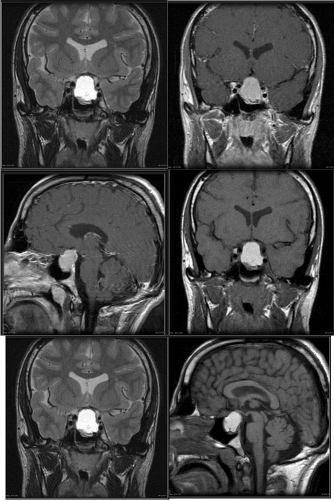

MRI of Head Nov. 01

1. A large pituitary tumor measuring 26x22mm isointense with brain, showing suprasellar extension, it shows calcifications and peripheral enhancement.

2. Brain, ventricles, & cisterns are normal, there is no shift of midline structures…

3. Conclusion: Pituitary Adenoma with suprasellar Extension.

A well-circumscribed mass is present within the expanded sellaturcica. This mass has suprasellar extension and demonstrates iso-intense signal on T1 weighted imaging, heterogeneous but predominantly low signal on T2 weighted imaging, and has predominantly peripheral enhancement, the lesion mildly bulges into the right cavernous sinus with no definite invasion. The optic chiasm is superiorly displaced by the mass and drapes over it. The lesion elevates anterior aspect of floor of the third ventricle without causing hydrocephalus.